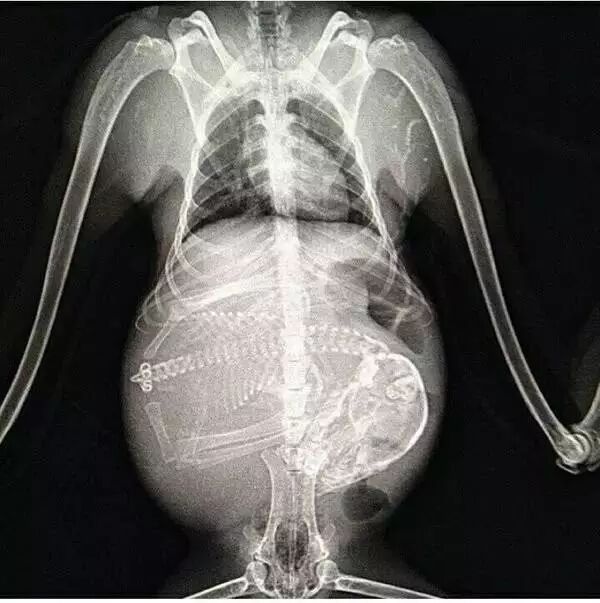

奇趣百科 涨姿势 · 17种怀孕动物X光照片,大开眼界!

人类的怀孕X光照片你可能看过,动物的就未必了,何况还是这么多种!

怀孕的狗